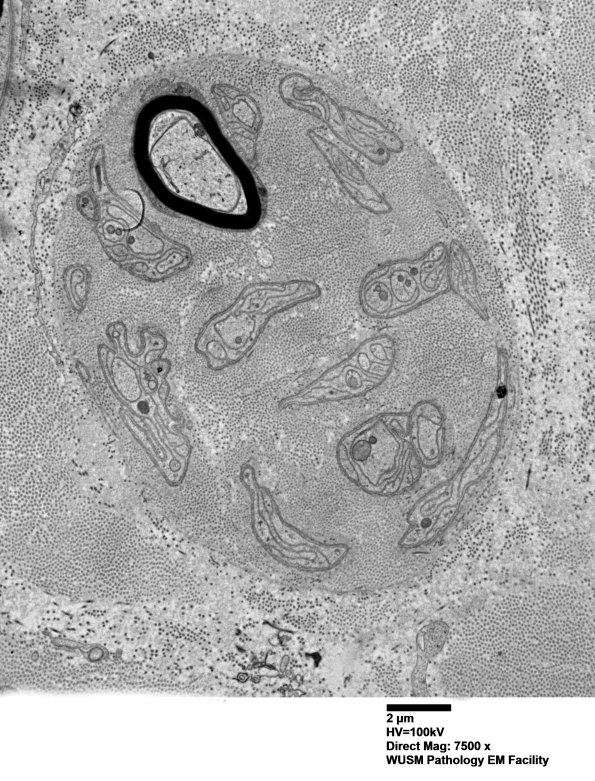

These examples have both normal and abnormal structures within the clusters. (Electron micrographs)